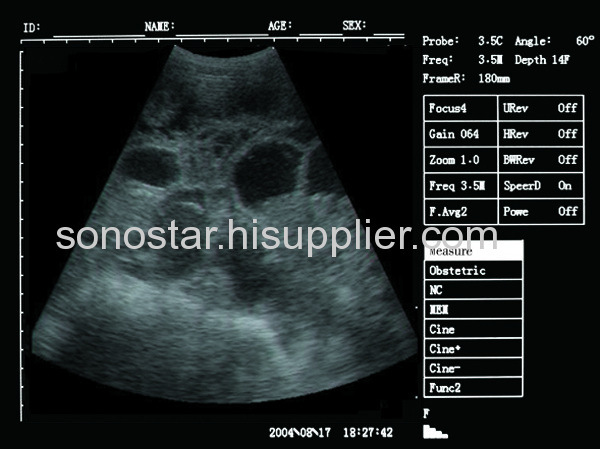

| Scanning mode: | B, 2B, 4B, B/M, M |

| Frequency Scope: | 2.0-9.0MHz, Multi-Frequency |

-Display mode: B, B+B, B+M, M, 4B

-Scanning range: Convex array 60°~150°

-Gain control: 8 segments TGC and overall gain can be adjusted respectively

-Image processing: 8 γ corrections, frame correlation, point correlation, line correlation,

digital filtering, digital edge enhancement and pseudo color processing, etc

-Image gray-scale: 256 levels

-Scanning line number: 512 lines/frame

-Frame rate: 30 frames/second

-Conventional measurements: distance, perimeter, area, volume

-Obstetric measurement: gestational weeks (BPD, GS, CRL, FL, HL, OFD, TTD, AC),

expected date of confinement and fetus weight, etc.